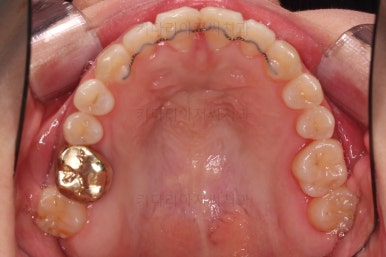

이번 부산교정 환자분은 교정치료 첫 단꼐로 악궁확장장치를 했는데요.

일반 확장 장치로는 불가하다는 판단이 되어 미니스크류를 활용한 악궁확장장치(MARPE)를 해주었어요.

이번 환자분은 일반 악궁확장장치로는 불가하다는 판단에 미니스크류를 이용한 악궁확장을 시행했고요.

입천장에 장치를 3개월 가량 유지하는 동안 치아에 브라켓을 부착하여 가지런하게 해줍니다.

이번 환자분이 선택하신 장치는 눈에 많이 띄는 윗니는 자가결찰 세라믹(데이몬 클리어, Damon clear), 아랫니는 자가결찰 메탈(엠파워 메탈, Empower metal)을 사용했어요.